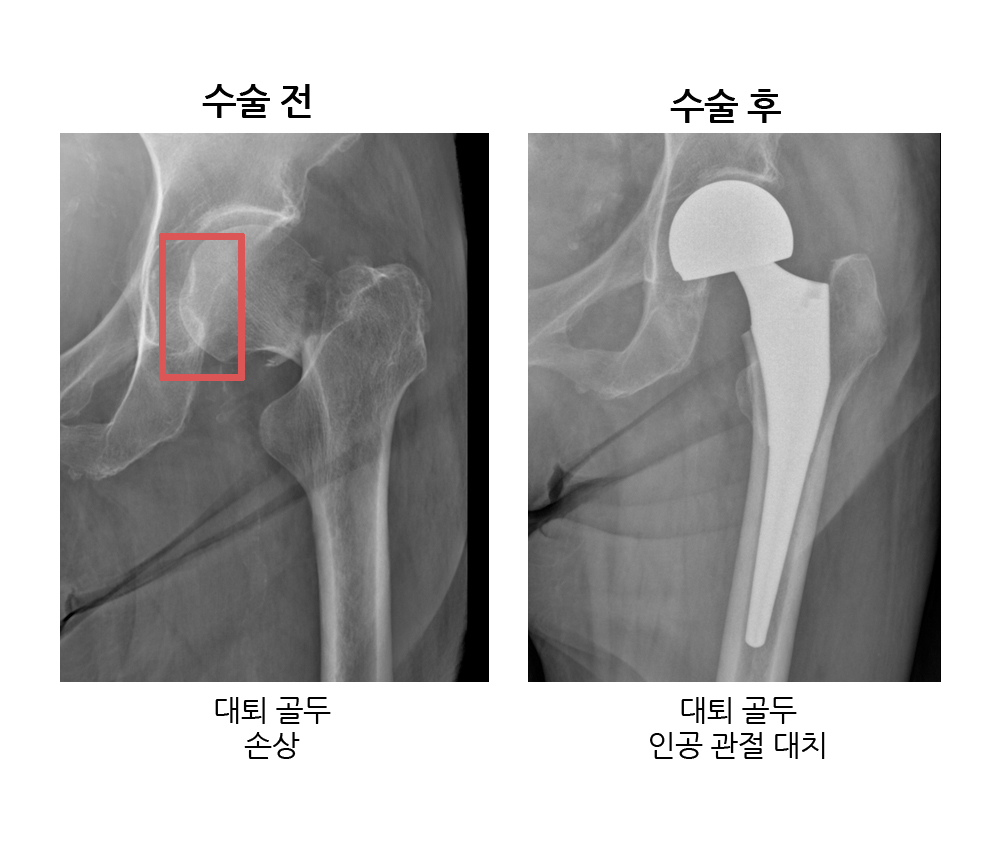

(고양이 ‘나비’ 엑스레이, 2021년 11월경 골반 골절) 수술은 계획대로 진행되었습니다. (1) 천장관절 탈구 우측 골반 탈구 (1-2) 비구 골절 우측 골반골 절제술 -> 고관절 절제술(FHNO) 시행

(2) 왼쪽 골반의 장골 날개 골절 – 부러진 뼈의 올바른 정렬

– 부러진 뼈에 나사를 삽입할 공간이 부족하여 나선형 골절은 핀과 나사로 고정하여 골절면의 안정성을 높이고 골절면을 기준으로 2/2개의 나사만 판재에 삽입하였다. 수술 후 X-ray Bum 수술 전후 X-ray Bum은 큰 수술을 잘 견뎌냈습니다. 너무 독특해요! ㅠ 수술 후 일주일간 입원했고 수술 후 4주간은 활동을 엄격히 제한할 예정입니다! 그것을 제거. 우리 범이는 정말 정말 착해요. ㅠㅠ 아프지만 만져주시는게 좋아요. 추락 사고가 어떻게 발생했는지는 모르겠지만 구조 대원이 그를 찾아서 구해줘서 기쁩니다. Bum은 구조대원들이 앞으로 그를 입양할 계획이라고 말했습니다! 감사해요! 우리 호랑이는 아주 아주 특별하고 원활한 운영에 너무 감사합니다! 내 범TT 너무 좋아! ! !